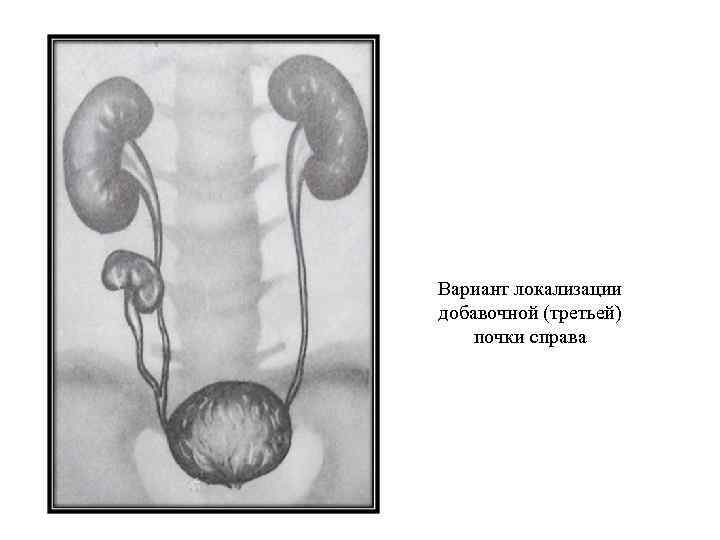

Вариант локализации добавочной (третьей) почки справа

Вариант локализации добавочной (третьей) почки справа